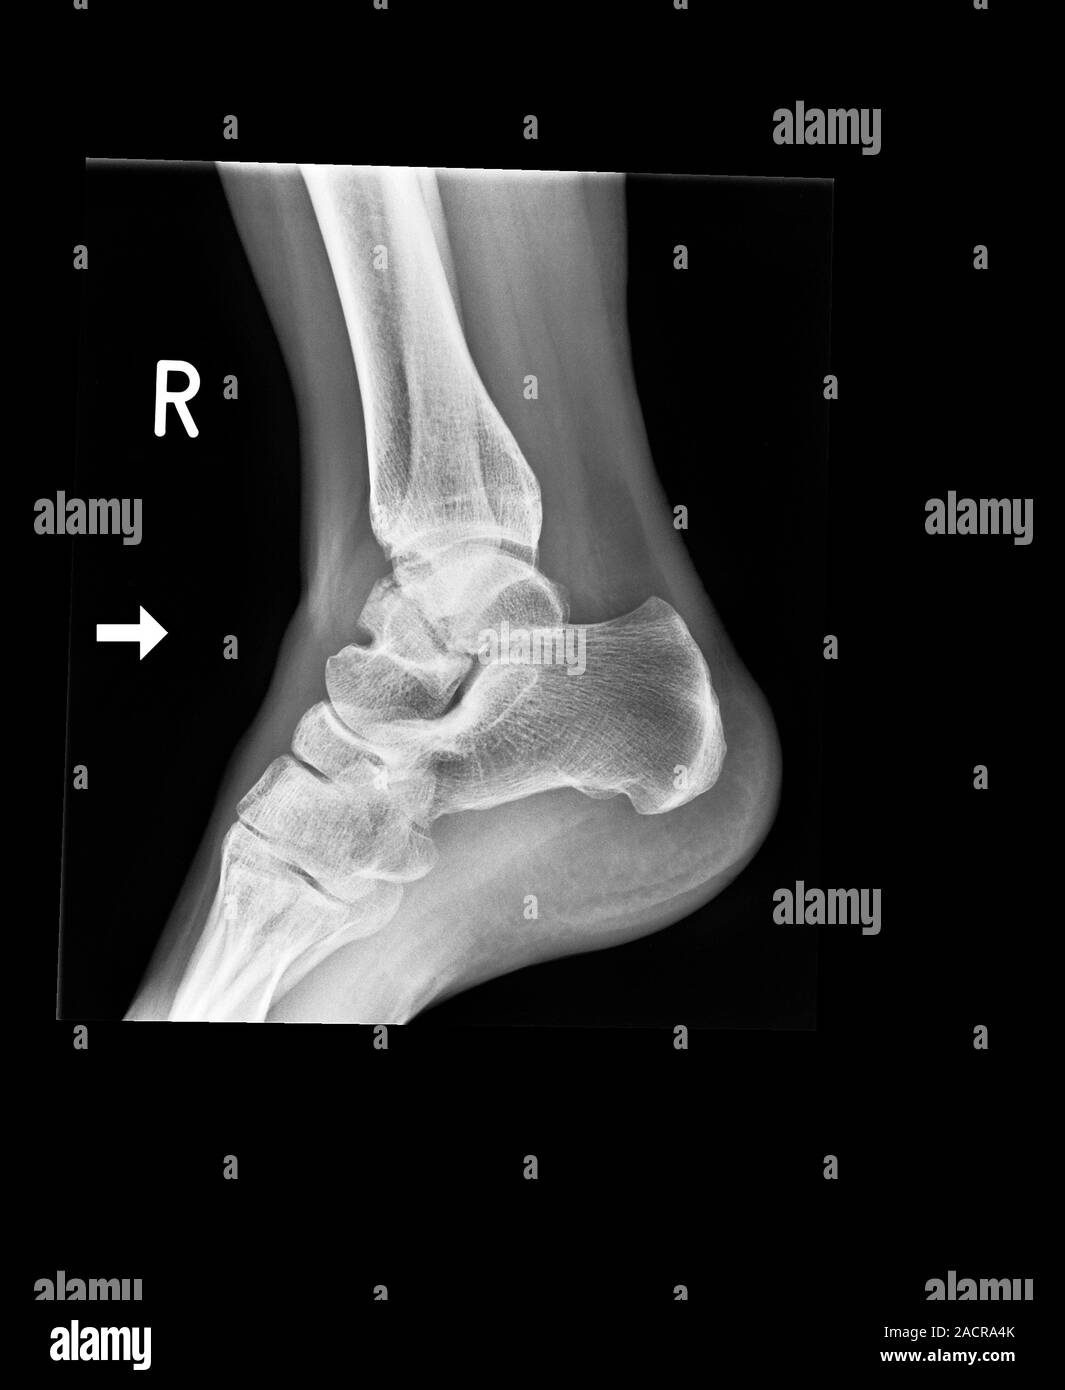

From www.alamy.com

Fractured ankle bones, Xray. The fracture is at lower left. For the same patient with the Ankle Bone Fracture X Ray An ankle fracture happens when you break one or. Ankle fractures are usually bony injuries involving the distal tibia (medial malleolus) or distal fibula (lateral malleolus). Ankle fractures account for ~10% of fractures encountered in trauma, preceded only in incidence by proximal femoral fractures in the lower limb. They can show where the bones are broken and if any of. Ankle Bone Fracture X Ray.